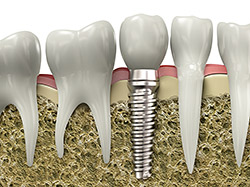

An implant is a synthetic tooth root in the shape of a post that is surgically placed into the jawbone. The “root” is usually made of titanium: the same material used in many replacement hips and knees, and a metal that is well-suited to pairing with human bone. A replacement tooth is then fixed to the post. The tooth can be either permanently attached or removable. Permanent teeth are more stable and feel more like natural teeth.

Single or Multiple Implants

Implants are versatile. If you are only missing one tooth, one implant plus one replacement tooth will do the trick. If you are missing several teeth in a row, a few strategically placed implants can support a permanent bridge (a set of replacement teeth). Similarly, if you have lost all of your teeth, a full bridge or full denture can be permanently fixed in your mouth with a strategic number of implants.